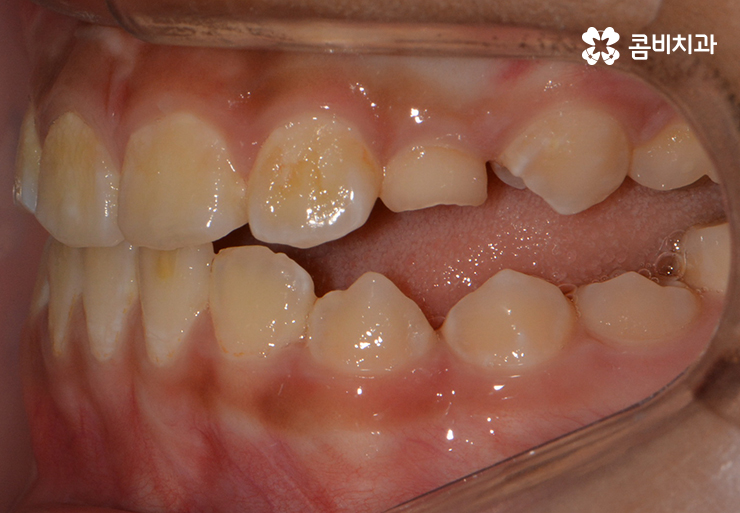

(3개월 정도 후 성장 조절 치료를 통해서 주걱턱이 점점 개선되고 있는 모습)

(반대교합, 주걱턱 교정치료가 시작된지 1년 후의 모습)

성장기치아교정의 큰 장점 중에 하나라면 성인에 비해서

진료 기간이 단축된다는 점인데 치아의 이동이 빠르고

치주조직이 빠르게 적응을 한다는 점에서도 유리합니다.

앞니가 반대로 물리고 있던 상황(주걱턱)에서 정상적으로 앞니가 물리게 되었음